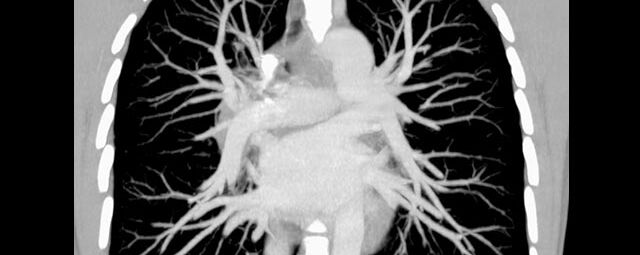

Thorax (Brustkorb)

• Entzündungen oder Tumore des Mediastinums und der Lunge

• Lungenembolie- Diagnostik

• hochauflösende Darstellung des Lungenparenchyms zur Abklärung chronischer interstitieller Erkrankungen wie z. B. Fibrosen, Emphysem, Bronchiektasen